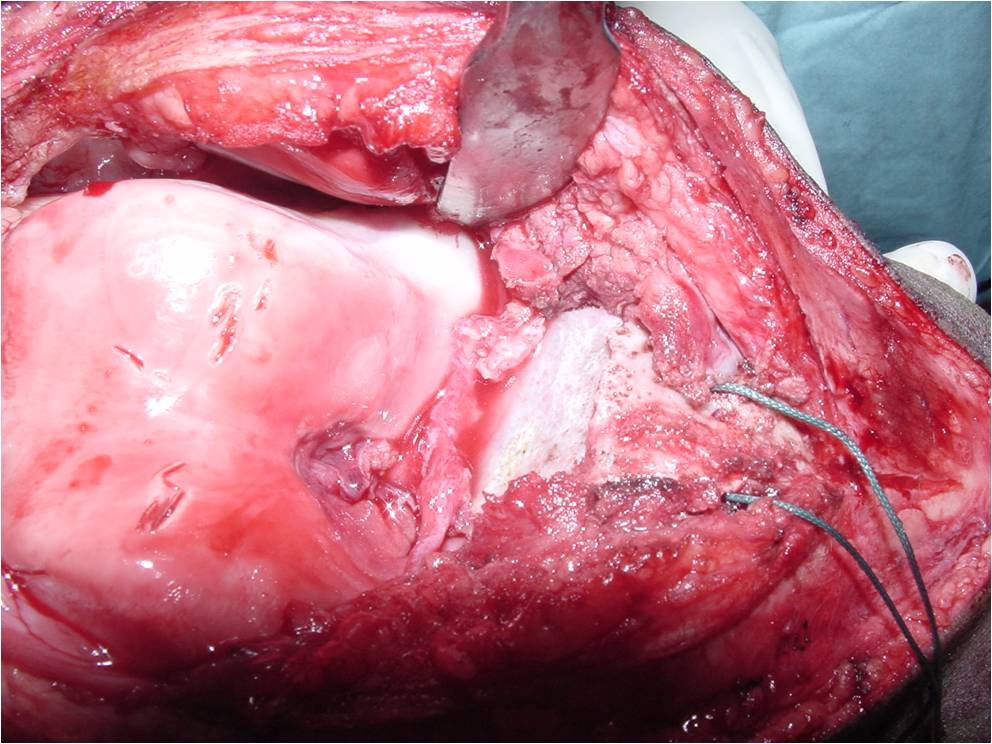

General Information Enchondroma is a benign indolent intramedullary hyaline cartilage neoplasm Accounts for 10% of all benign osseous tumors Limited growth, most lesions are less than 5 cm in maximal dimension Bones grow from a cartilaginous growth plate that...